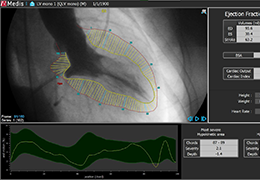

ANYTHINK 经导管主动脉瓣膜置换术分析系统